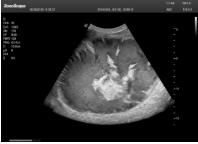

1單晶體凸陣探頭

采用了單晶體探頭材料,探頭面是凸面,接觸面小,成像視野呈扇形,應(yīng)用廣泛,常應(yīng)用于腹部、婦產(chǎn)、肺部等相對部位較深的臟器。

超聲圖像是探頭和系統(tǒng)平臺(tái)緊密結(jié)合的產(chǎn)物,因此在同一臺(tái)機(jī)器上,軟件、硬件都需要達(dá)到單晶探頭的要求。

肝癌